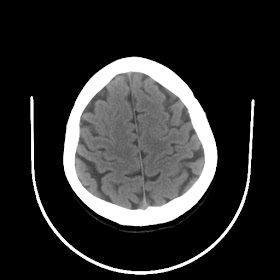

A 33 years old woman with protruding eyeballs & hyperthyroidism since 2 years